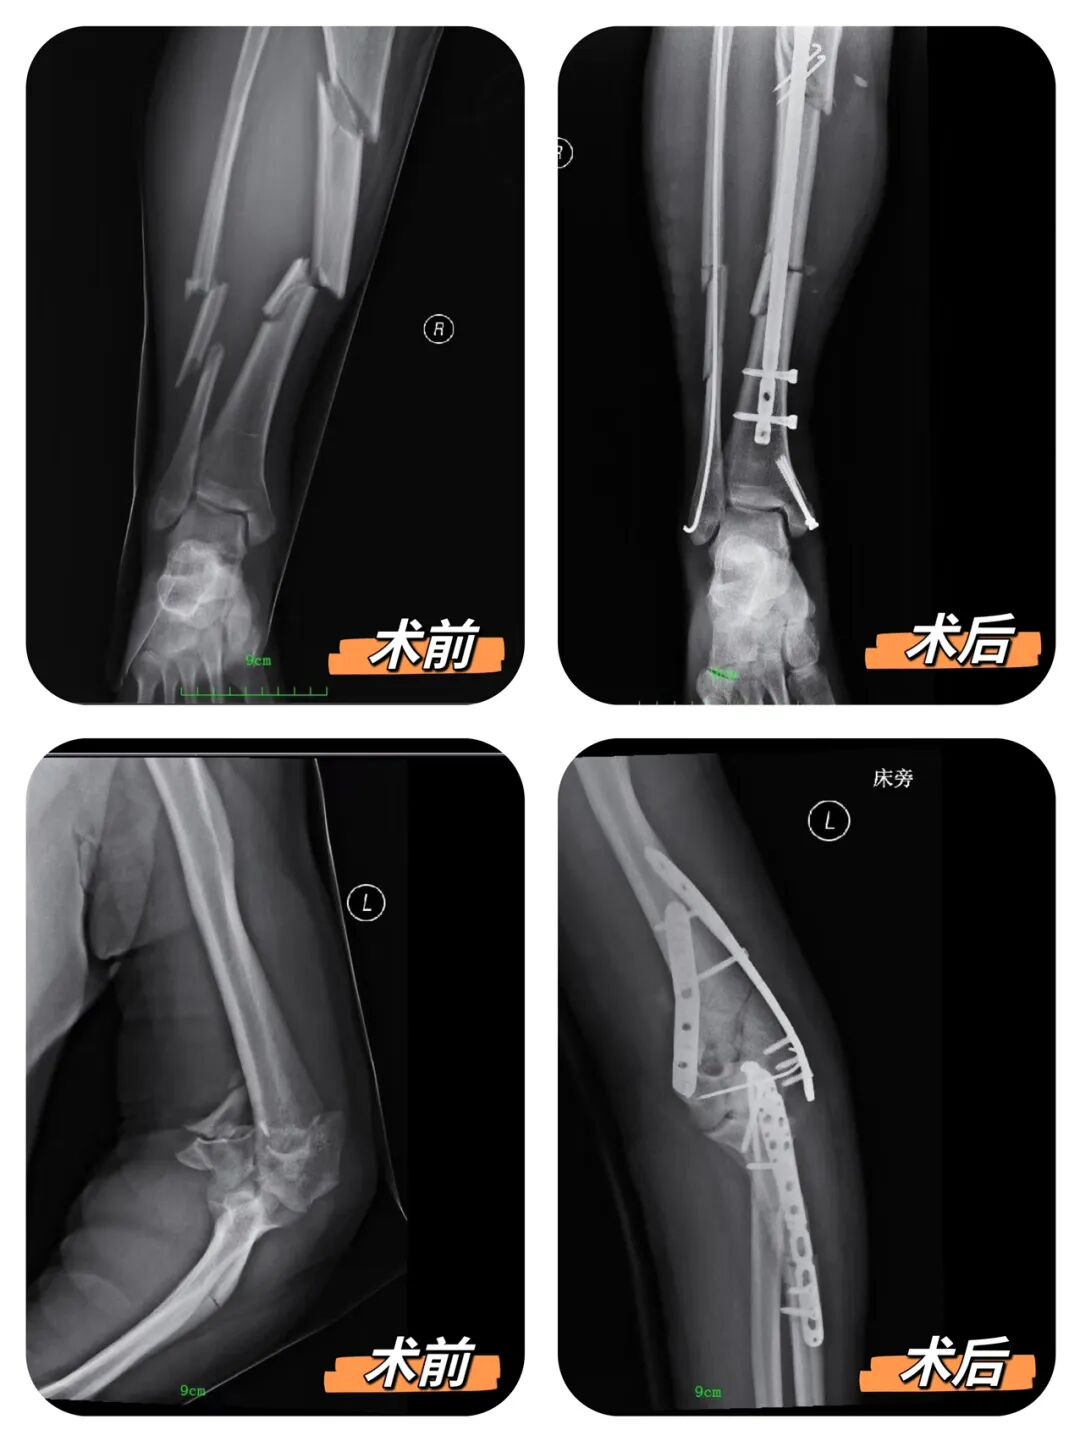

创伤专业